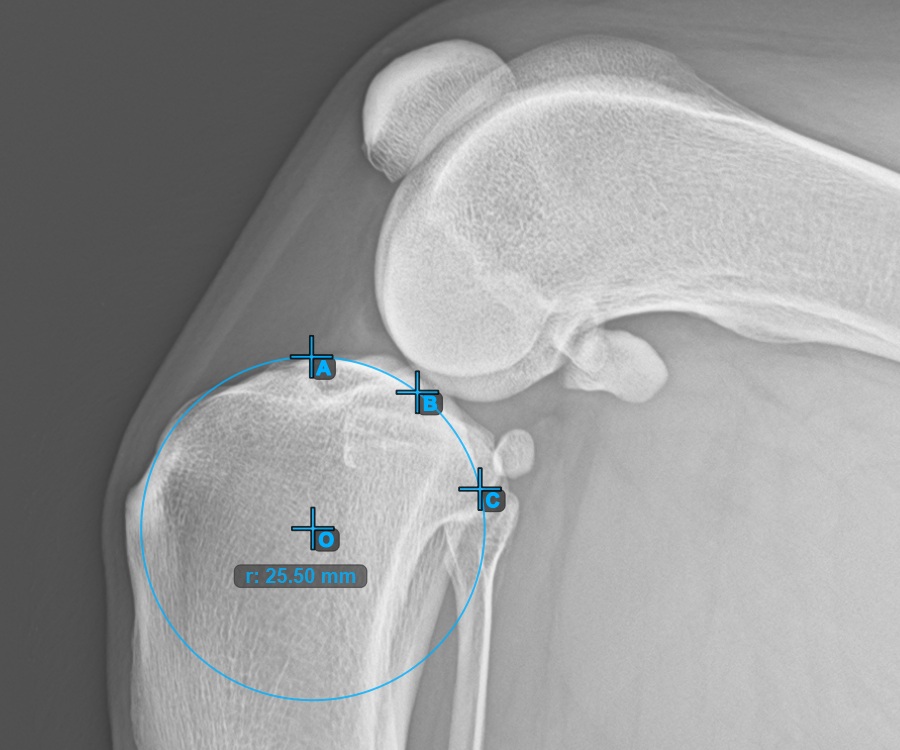

Markieren Sie die drei Punkte am Hauptkondylus des Tibiaknochens (Medialis Tibialis). Unabhängig von der Reihenfolge stellen Sie sicher, dass Sie den vordersten Punkt, den hintersten Punkt und den Mittelpunkt des Medialis Tibialis markieren. Basierend auf den drei gesetzten Punkten wird automatisch ein Kreis konstruiert.

Das Bild unten zeigt die typische Platzierung der drei Punkte am Condylus Medialis Tibialis.